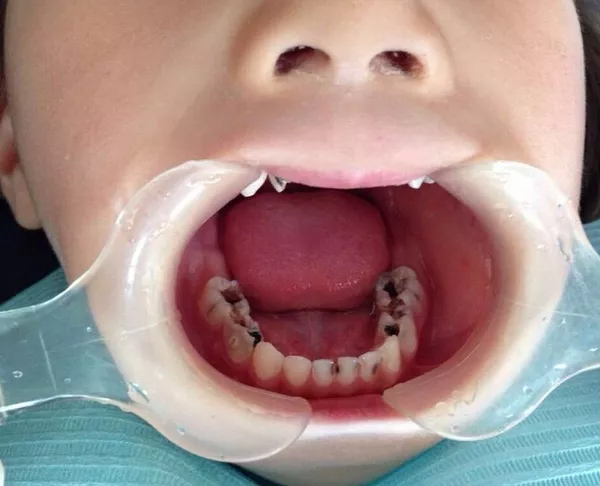

然而并没有好好地护理,乳牙蛀了,刚开始是这样的。

乳牙

隔壁的大妈说,乳牙要换的,不用补。然后就变成这样了。

家长开始着急,然而村口摆地摊“100块种牙”的老大爷又说了,“这算事儿吗?换牙就好了!”于是,牙齿就变成这样了。